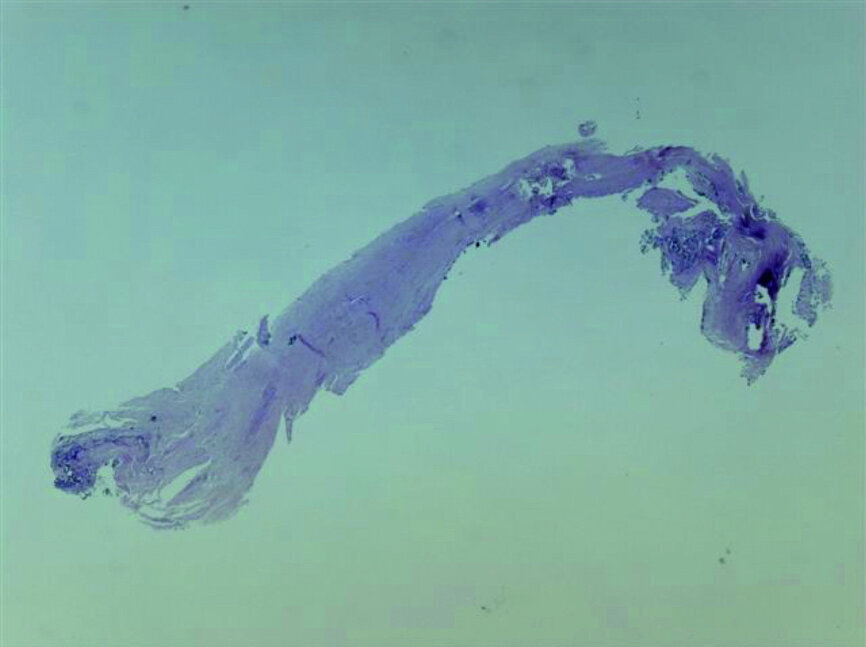

Fig. 20: Tissue removed from the endodontic space three months after transplantation (H&E stain; 2× magnification).

Fig. 21: Tissue removed from the endodontic space three months after transplantation (H&E stain; 4× magnification).

Pulp histology and necessity of endodontic treatment

Full development of the root can be expected when surgery is performed under ideal circumstances and Hertwig’s epithelial sheath is preserved; moreover, it depends on the root length at the moment of transplantation. [14] Teeth in the early stages of root development show less post-transplantation root growth than those with more mature roots, but incompletely formed apices. [15]Pulp regeneration and revascularisation are expected when the apical foramen displays at least a diameter of 1 mm radiographically. [16] Obliteration of the root canal is to be expected, owing to ingrowth of connective tissue. When roots are completely developed, root canal therapy is indicated. [17] In one of our cases, pulp histology was performed on the tissue extracted from root canals, and connective tissue with low vascularity was found (Figs. 20 & 21).